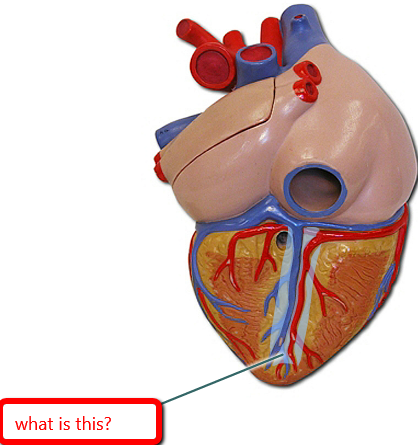

Apex (of the heart)

Chordae tendineae

Papillary muscles